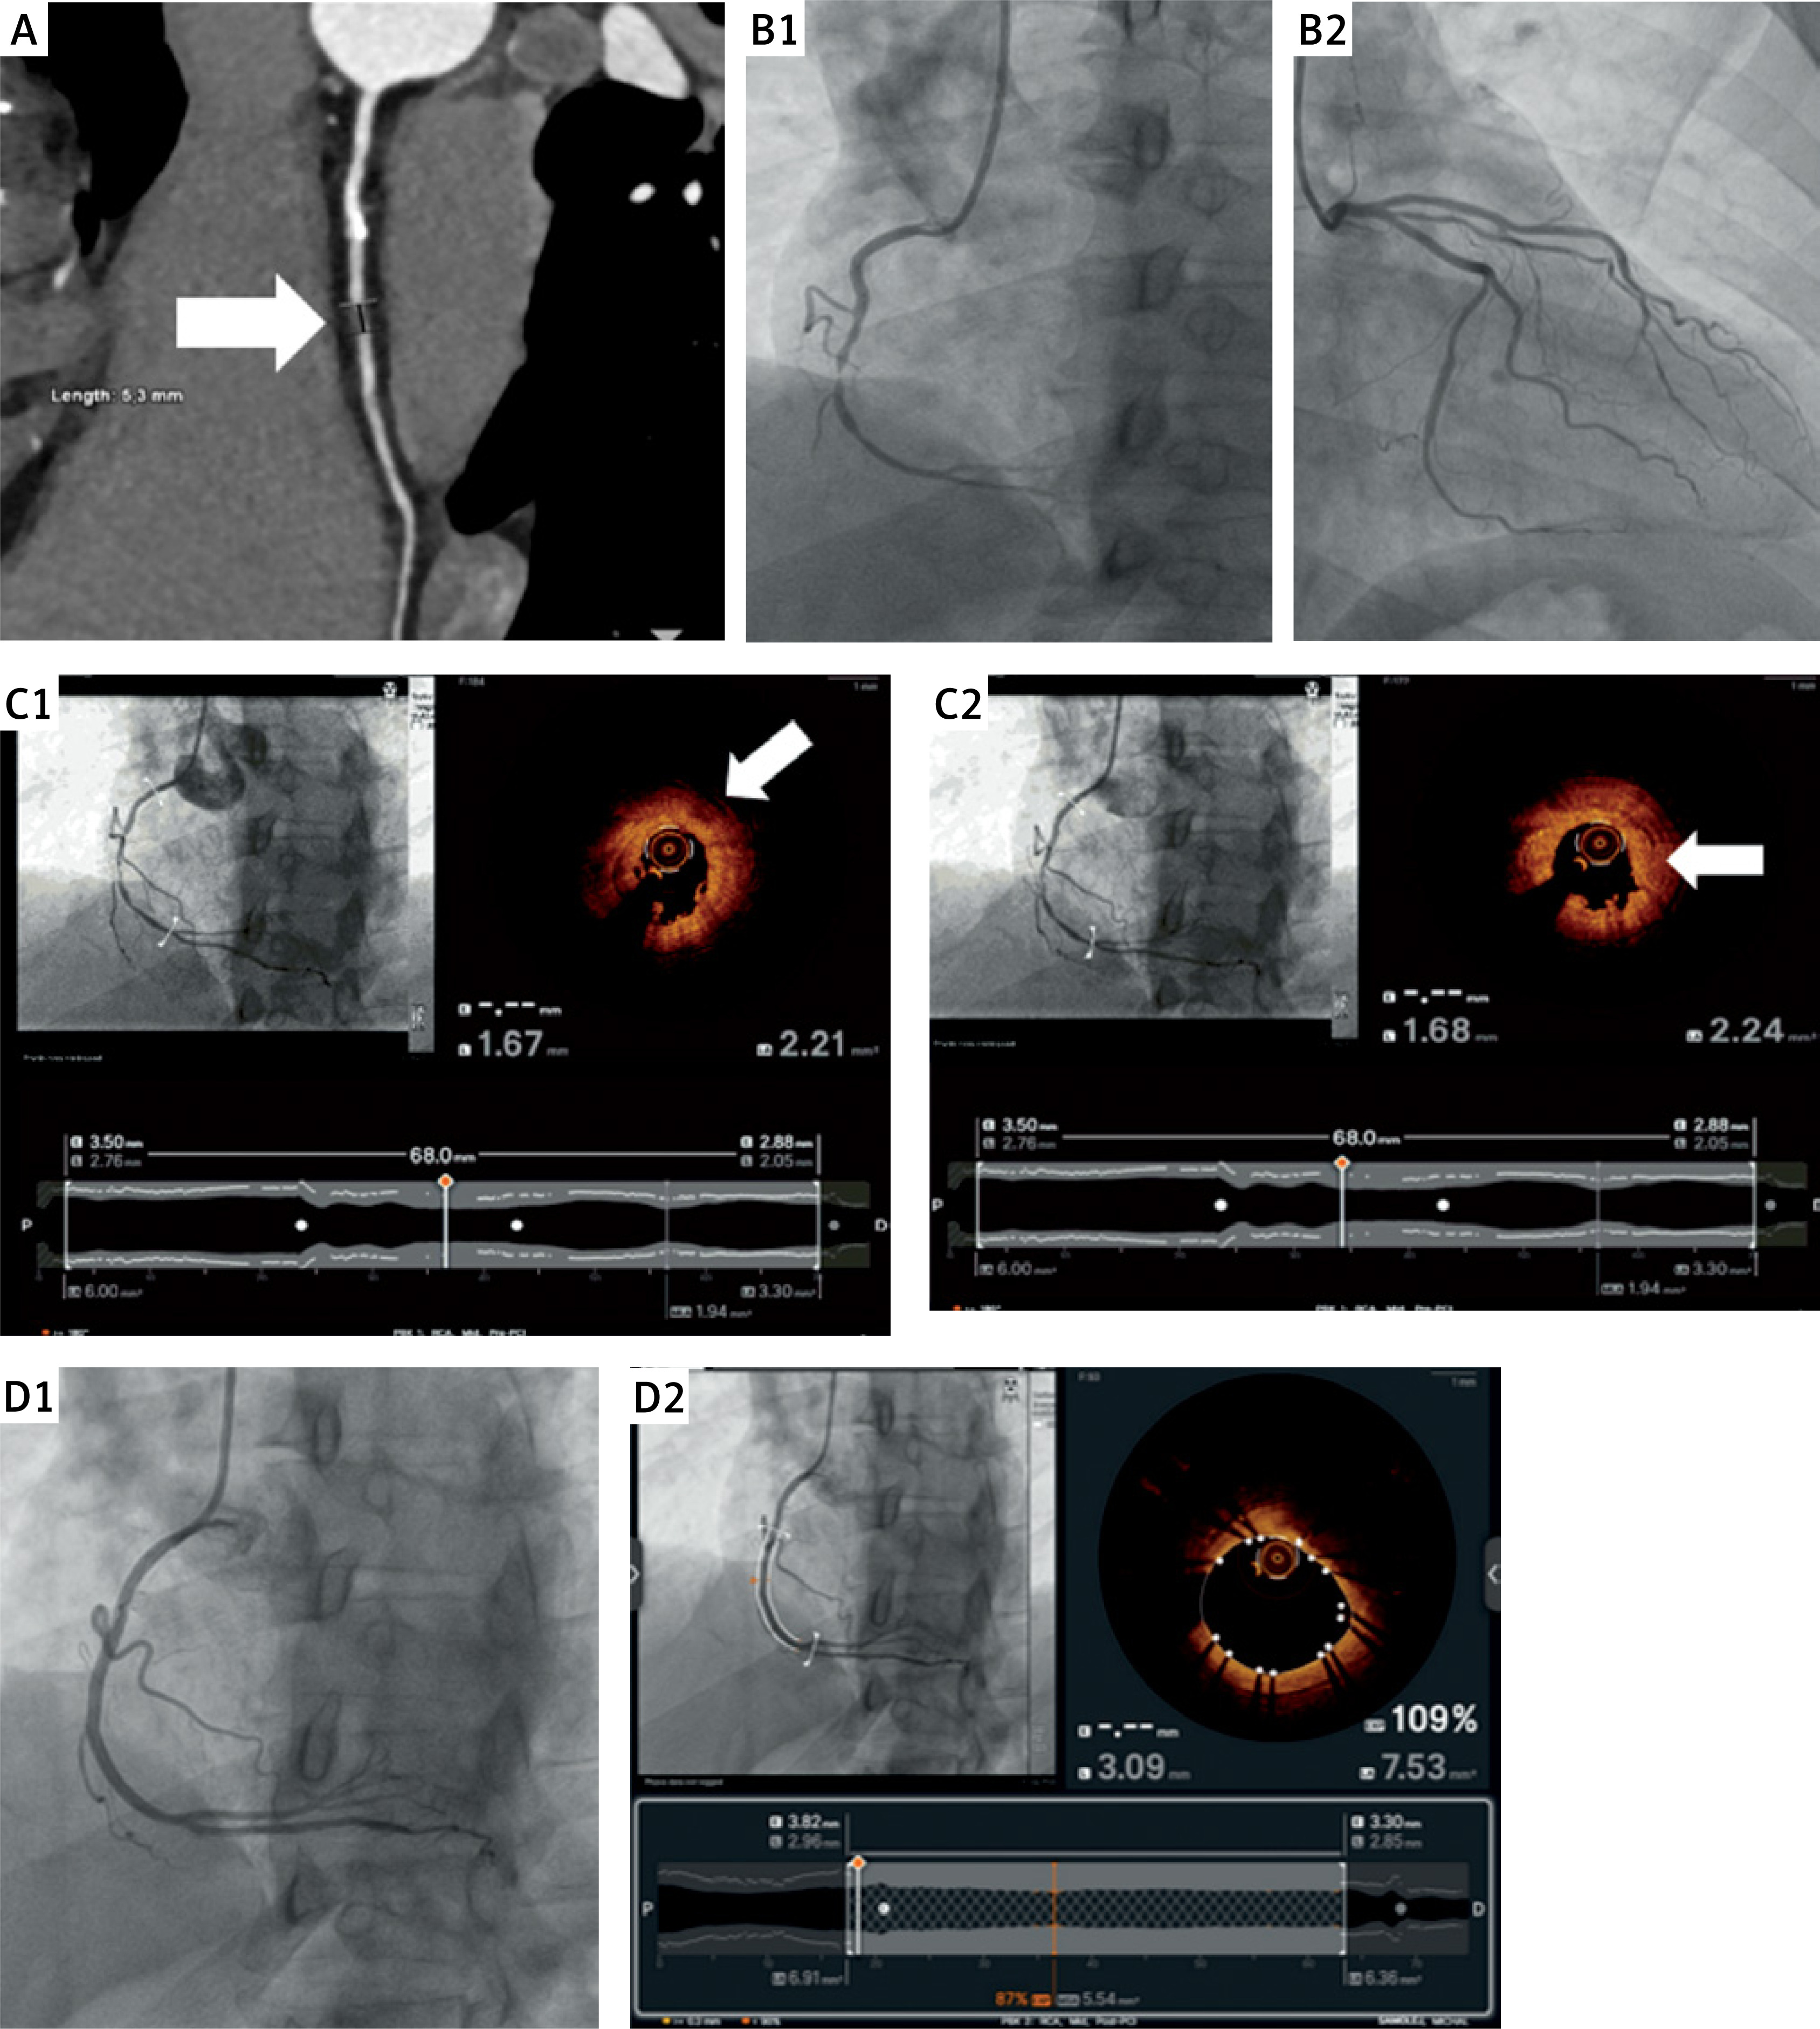

Figure 1

A – computed angiography tomography of the right coronary artery (RCA) (arrow: coronary artery calcification (CAC)). B1 – coronary angiography of RCA, before percutaneous coronary intervention (PCI) (arrow: CAC). B2 – coronary angiography of the left coronary artery (LCA), before PCI. C1 – optical coherence tomography of RCA, before PCI (arrow: lipid core). C2 – optical coherence tomography of RCA, before PCI, arrow: site of rupture). D1 – angiographic image of RCA, just after PCI. D2 – optical coherence tomography of RCA, just after PCI

The patient was scheduled for urgent coronary angiography and admitted on the next day. While being transported to the catheterization laboratory on foot, the patient reported chest pain. The electrocardiography (ECG) performed in the catheterization laboratory showed ST segment elevation in leads II, III, and aVF. Coronary angiography revealed a critical stenosis of 99% in the middle segment of the RCA (Figure 1 B1) and only minor plaques in the left coronary artery (LCA) (Figure 1 B2). Optical coherence tomography (OCT) confirmed the presence of thin-cap fibroatheroma with lipid core (Figure 1 C1) and ruptured atherosclerotic plaque with a thrombus (Figure 1 C2), and the patient was deemed eligible for immediate coronary angioplasty. Drug-eluting stent implantation (Ultimaster 2.75 × 44 mm, 20 atm) was performed under optical coherence tomography (OCT) guidance.

The result of the procedure was optimal (Figure 1 D1). It was confirmed in OCT, which showed a minimal stent area of 5.5 mm2 and good apposition of the stent (Figure 1 D2). A day later, the patient was discharged home in good condition.